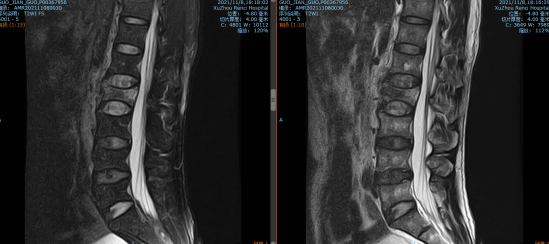

11月初山东的郭大叔如往常一样在厂里干活,突然设备掉落砸伤了其腰背部,当时他就不能动了,家人、同事连忙将他送到当地医院检查,结果ct显示大叔的L2椎体骨折。这可急坏了大叔的家人,家人找亲朋好友四处打听,得知betway在线登陆可以做脊柱微创手术,连夜带着郭大叔来我院就诊。

脊柱科孟磊副主任医师为大叔检查后,发现他不单单是腰椎骨折,还有胸骨体骨折、腰椎横突骨折、棘突骨折、右侧第3-5、8肋骨骨折伴有肺部挫伤以及胸腔积液。患者家属表示,大叔是家中的主要劳动力,请求孟医生一定要帮帮他们一家!孟医生手术团队决定采用机器人辅助下腰椎骨折复位内固定术。和传统手术相比,天玑骨科机器人辅助更安全高效,手术切口小、定位精确无误差、伤口小、疼痛轻、恢复快。